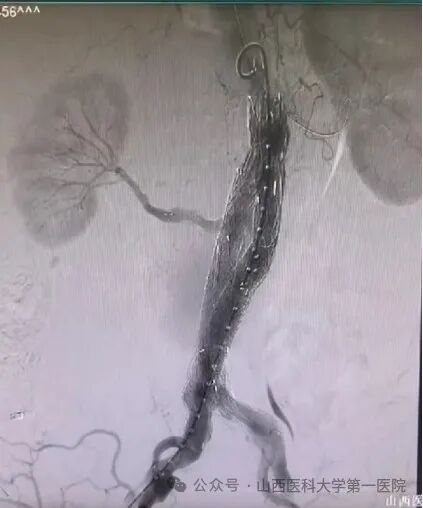

图为术后CTA复查,双肾动脉血供正常,腹主动脉覆膜支架内血流正常,无明显内漏。 这种纯腔内治疗腹主动脉瘤并重建双肾动脉的手术难度很高,在国内顶尖医院也属少见。在麻醉科、手术室的通力合作下,患者手术获得成功,术后恢复顺利,经CTA复查双肾动脉血供正常,腹主动脉覆膜支架内血流正常,无明显内漏。